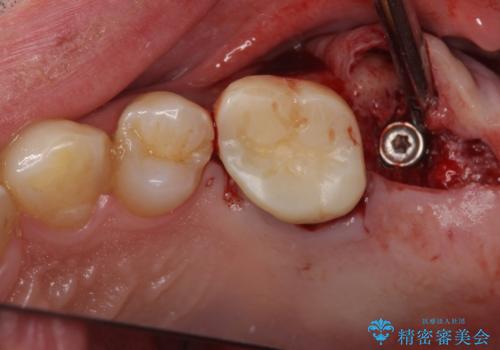

奥の歯は抜歯が必要なため、インプラント埋入による補綴治療を行うこととしました。

術後半年でレントゲン写真を撮影したところ、インプラント周りの骨は安定しており、根管治療を行った歯周辺の病変はきれいに改善されていました。